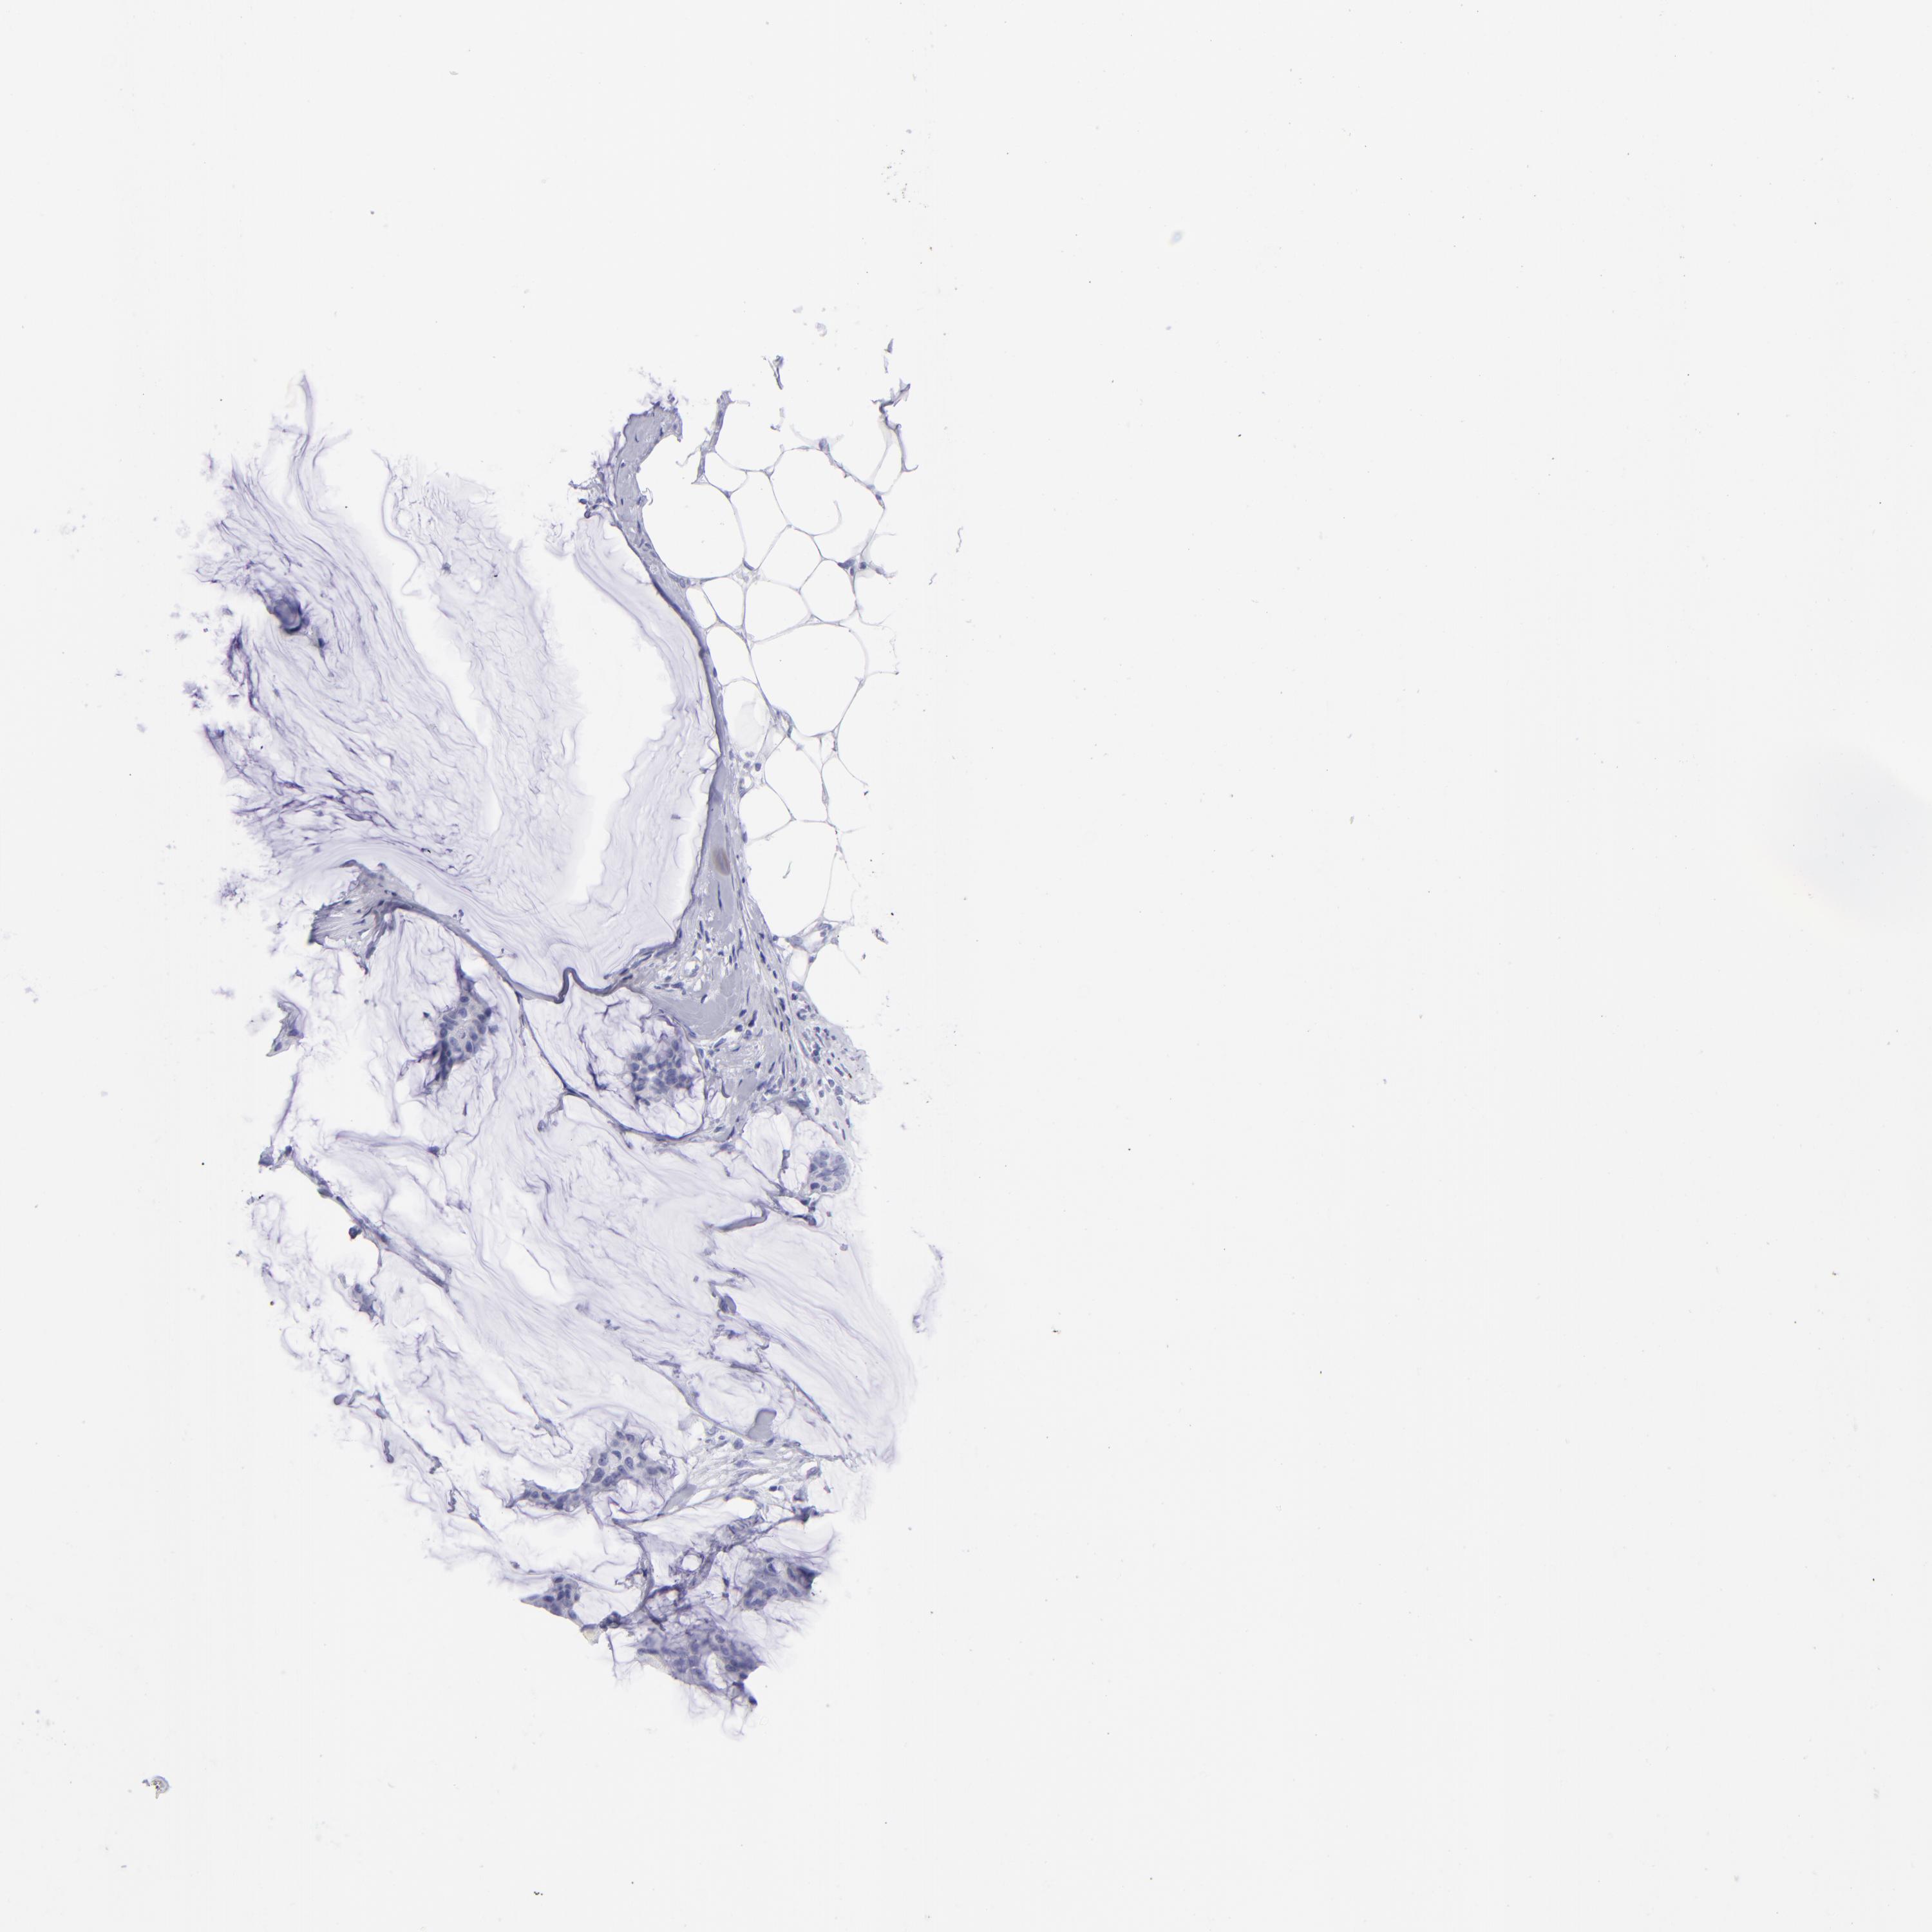

Breast cancer

Human cancer